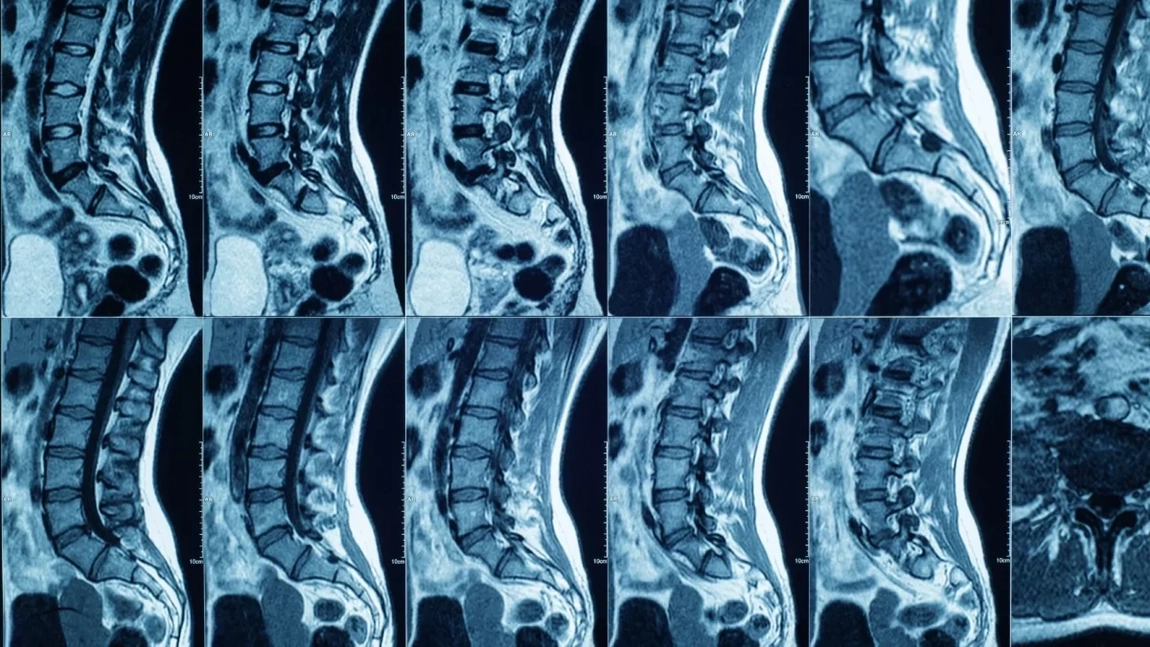

RMN-ul la coloana lombară este o investigație imagistică avansată, care folosește câmpuri magnetice și unde radio pentru a obține imagini detaliate ale structurilor interne. Spre deosebire de radiografie sau tomografie computerizată, această procedură nu utilizează radiații ionizante, ceea ce o face mai sigură pentru pacient.

Această analiză este recomandată frecvent în cazul durerilor lombare persistente, herniilor de disc, suspiciunilor de stenoză spinală, inflamațiilor sau traumatismelor. Medicii se bazează pe imaginile obținute pentru a observa discurile intervertebrale, nervii, măduva spinării și țesuturile moi din jur. Astfel, diagnosticul este mult mai precis, iar tratamentul poate fi adaptat corect.

De asemenea, RMN-ul lombar este util și pentru monitorizarea evoluției unei afecțiuni deja cunoscute sau pentru evaluarea eficienței unui tratament. Deși procedura poate părea intimidantă pentru unii pacienți, aceasta este nedureroasă și durează, în medie, între 20 și 40 de minute, în funcție de complexitatea investigației.